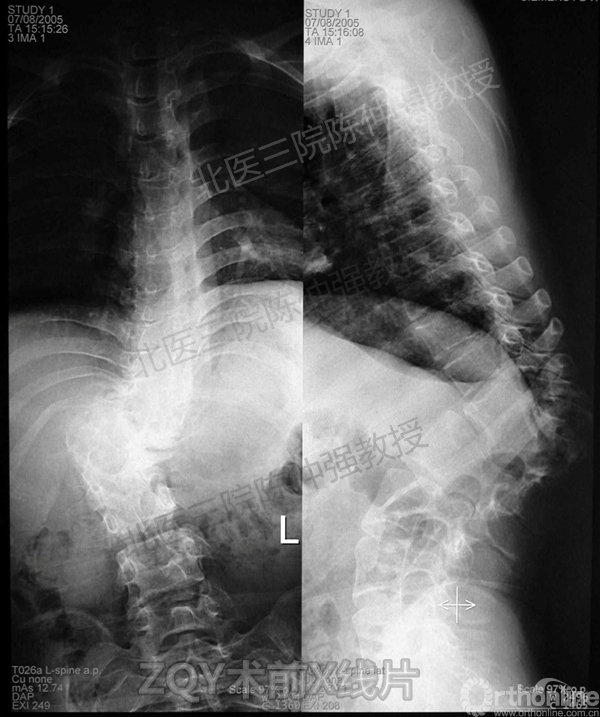

陈仲强教授病例分享

2005年,陈仲强教授在AOSpine年会上分享了一例胸腰椎陈旧结核性侧后凸畸形病例。资料如下:

ZQY术前

患者女性17岁,胸腰椎陈旧结核性侧后凸畸形,局部呈“麻花状”扭转,无神经功能受损表现。2005年,陈仲强教授带领团队实施后路+侧前方联合入路脊柱节段切除、双轴旋转矫形术。术后患者外观显著改善,神经功能正常。术后随访证实患者截骨矫形节段骨性融合良好,矫形效果持续良好。